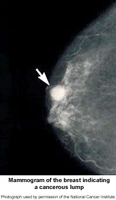

Picture of mammogram of the breast indicating a cancerous lump

• Calcifications, tiny mineral deposits within the breast tissue. There are two categories of calcifications:

• Masses, which may occur with or without associated calcifications, and may be due to different causes, including:

• breast cancer